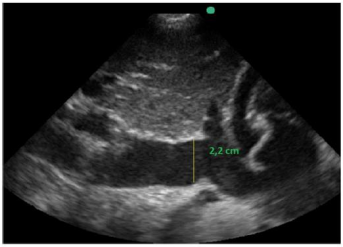

Também foi feita a mensuração da cava na janela subcostal 4 câmaras caval. O seu valor é maior de 2,2 cm e tem variabiliadade menor que 50% aos movimentos respiratórios ainda em ventilação espontânea, conforme a imagem apresentada.